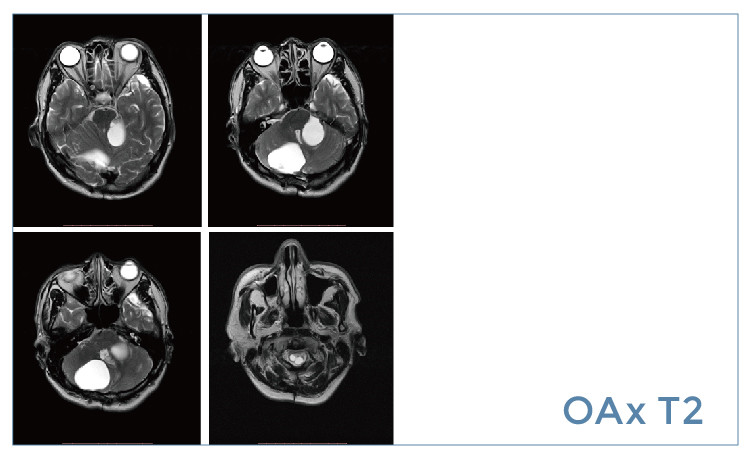

【朗润影像档案】磁共振影像病例分享(编号20190614)